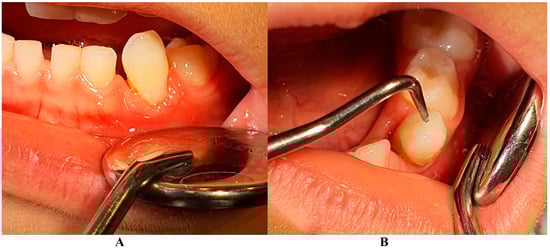

Figure 2.

(A,B) Intra-oral cavity general aspect (in early August) with the localized temporary canine problem that led to the LPP diagnosis.

On the other hand, when the first Stage IV grade C localized periodontitis/LPP diagnosis was established (2 August), the clinical examination showed an increased mobility of the temporary lower left canine due to massive bone and periodontal ligament loss, associated with a localized inflammation of the free gingival margin around the tooth, and with small amounts of dental plaque due to difficulties with oral hygiene (Figure 2 and Figure 3). No other plaque deposits, inflamed gingiva, or teeth mobility issues were detected during the clinical examination. When this information was correlated with the radiological examination from two months prior (19 June, Figure 1), with localized bone loss, the diagnosis based on clinical and radiological data was confirmed, with no need for further radiological examination. Moreover, the blood test with higher levels of lymphocytes [2,14] also confirmed Stage IV grade C localized periodontitis/LPP diagnosis. To assess the periodontal pocket bacteria responsible for this atypical LPP case (i.e., temporary molars/incisors are usually involved [1,2,10], rather than the canine, as in this case), a canine periodontal sulcus secretion test was sampled and sent to the laboratory.

A rapid Stage IV grade C localized periodontitis/LPP diagnosis is essential, since the aggressive auto-immune response to bacteria can rapidly lead to a resorptive process [1,2,3,4,5,6,7,8,9,11]. Thus, a simple bacterial test to identify the pathogenic bacterium types would provide both diagnostic confirmation and justification for antibiotic treatment [2,3,11,12,13,14,15]. If LPP disorder is identified early, there is time to wait (i.e., usually up to two weeks) for lab test results, and only then should antibiotic therapy proceed [5,6,9,10,16,17,18]. However, if the LPP diagnosis is late (as it was herein), antibiotic treatment must be started, with a combination of two large-spectrum antibiotics (amoxicillin and metronidazole) to cover most bacterial types [5,6,9,10,16,17,18]. It must be emphasized that LPP usually comes without or with very few plaque deposits (as the case herein showed—see Figure 1, Figure 2, Figure 3 and Figure 4), with little influence over surrounding gingival inflammation [1,2,4,5,6,7,8,9,10].